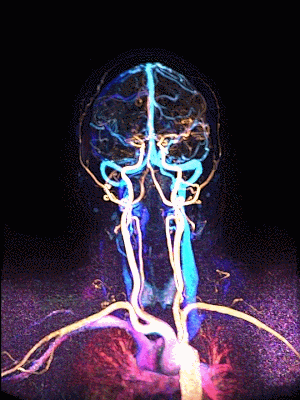

측부혈류영상과 동시 생성하는

동맥영상(Arteriography), 정맥영상(Venography), 역동적 혈관영상(Dynamic Angiography)

추가 촬영없이 측부혈류영상과 동시에 생성하는 세계최초 딥클루의 원천 기술

Simultaneous Vascular imaging

3D 동정맥영상

3D 동맥영상

3D 정맥영상

4D 혈관영상